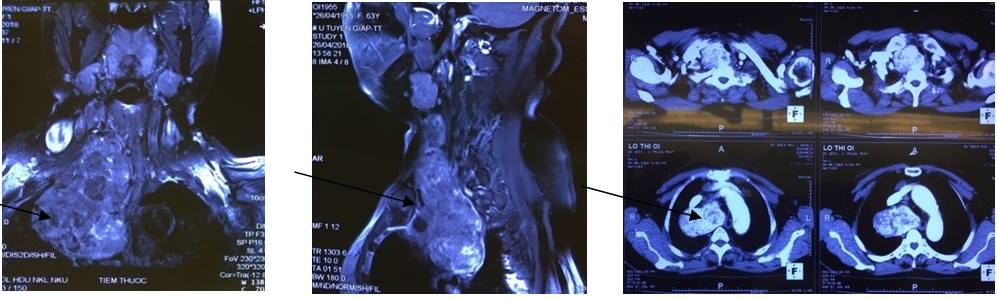

Triệu chứng ngày càng nặng, bệnh nhân đi khám ở bệnh viện tỉnh mới phát hiện ra một khối u lớn đã có dấu hiệu chèn ép vào khí quản và thực quản. Bệnh nhân được chuyển tuyến lên Bệnh viện Bạch Mai. Kết quả chụp Cắt lớp vi tính và cộng hưởng từ thấy khối u kích thước lớn 10x80x50mm sa vào trung thất, đè đẩy toàn bộ khí quản sang bên đối diện gây ảnh hưởng nghiêm trọng đến chức năng hô hấp: Rối loạn thông khí hạn chế mức độ vừa đến nhiều – đó là kết quả đo chức năng hô hấp và sinh thiết khối u trước mổ thấy bướu giáp keo lành tính.

| Hình ảnh khối u trên phim Cắt lớp vi tính và Cộng hưởng từ |